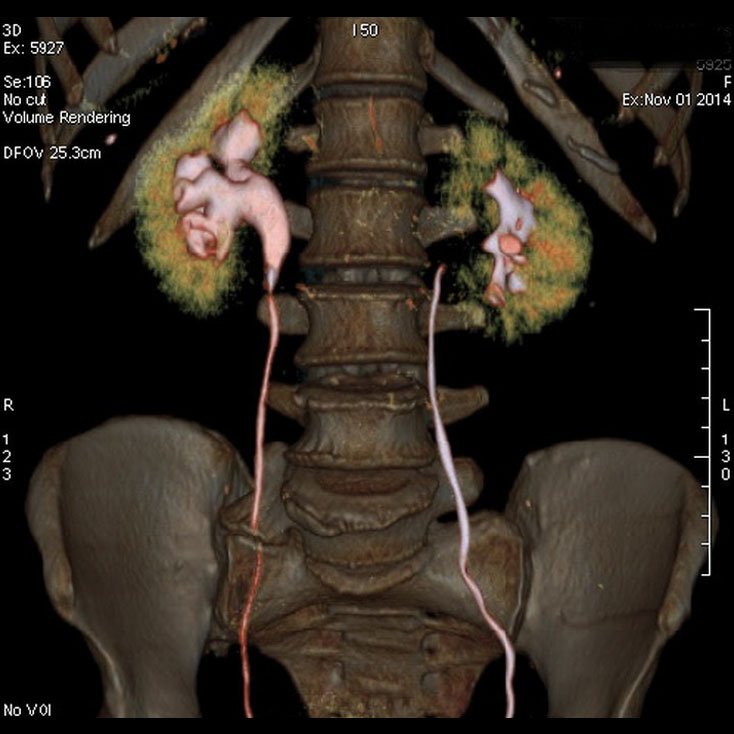

3D CT IVP

CT Kidney

Kidney Angiography